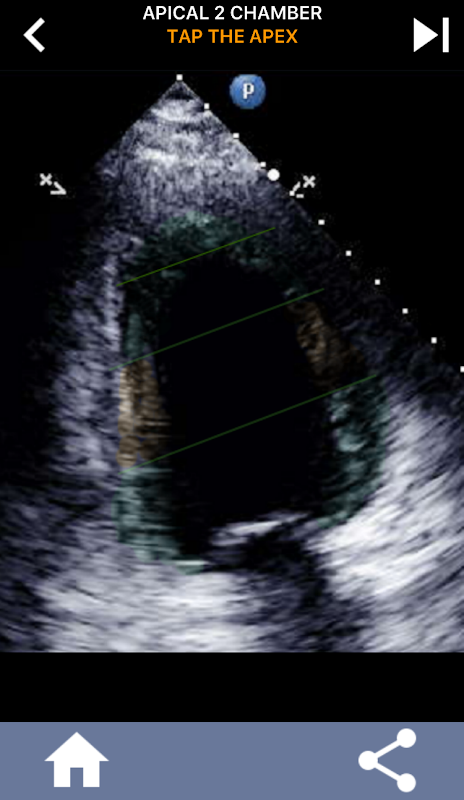

Snel leren het AHA 17 segment hart model, van essentieel belang voor ALLE echo studenten!

Het is van essentieel belang voor echocardiografen met ultrasound om de hartsegmentatie van het hart van de American Heart Association in 17 segmenten te leren, wat de standaard is die veel wordt gebruikt door vele andere beeldvormingsmodaliteiten zoals magnetische resonantiebeeldvorming, nucleaire kerntests, enz ... om de locatie te beschrijven van de getroffen segmenten en functie. Vaak vraagt de persoon die je echo leest, "wat heb je gezien?" en antwoorden met een exacte locatie van het getroffen gebied is wat wordt verwacht.

Deze app bevat alle echoviews die het AHA-gesegmenteerde myocardium tonen en zal je vragen het juiste segment te tikken. Persoonlijk vind ik dat repetitieve quizzing het beste werkt voor mij als ik het onderwerp snel moet leren / onthouden. Als je een echografie-student bent die echo / TTE studeert, denk ik dat dit een uitstekende aanvulling op je studie zou zijn.